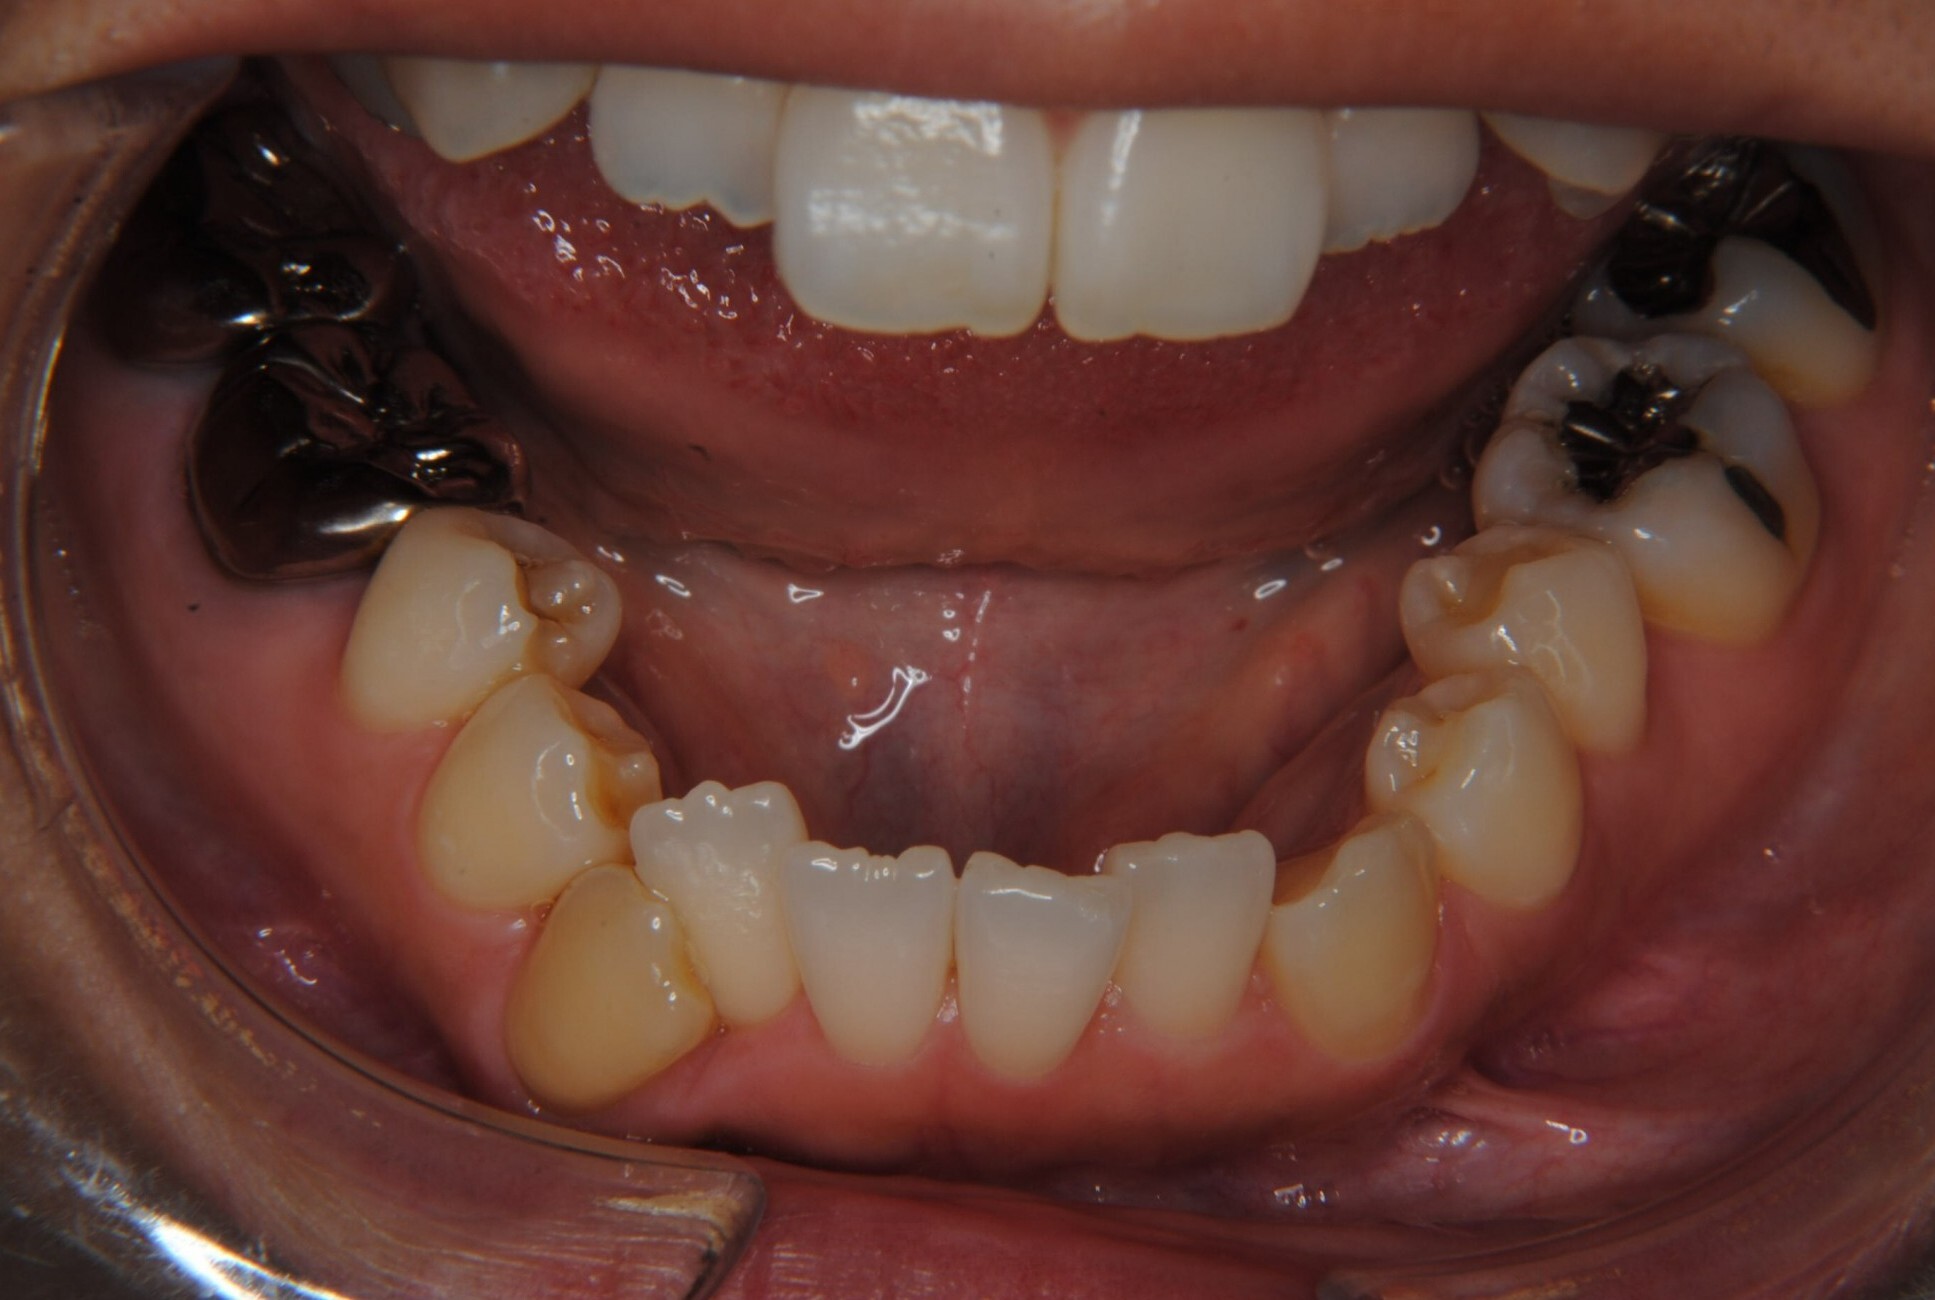

①主訴:八重歯、前歯のガタガタ、真ん中の不一致を治したい

②診断名:AngleⅠ級叢生

④治療に用いた主な装置:マルチブラケット装置(T21ブラケット)

⑤抜歯部位:上下左右第一小臼歯